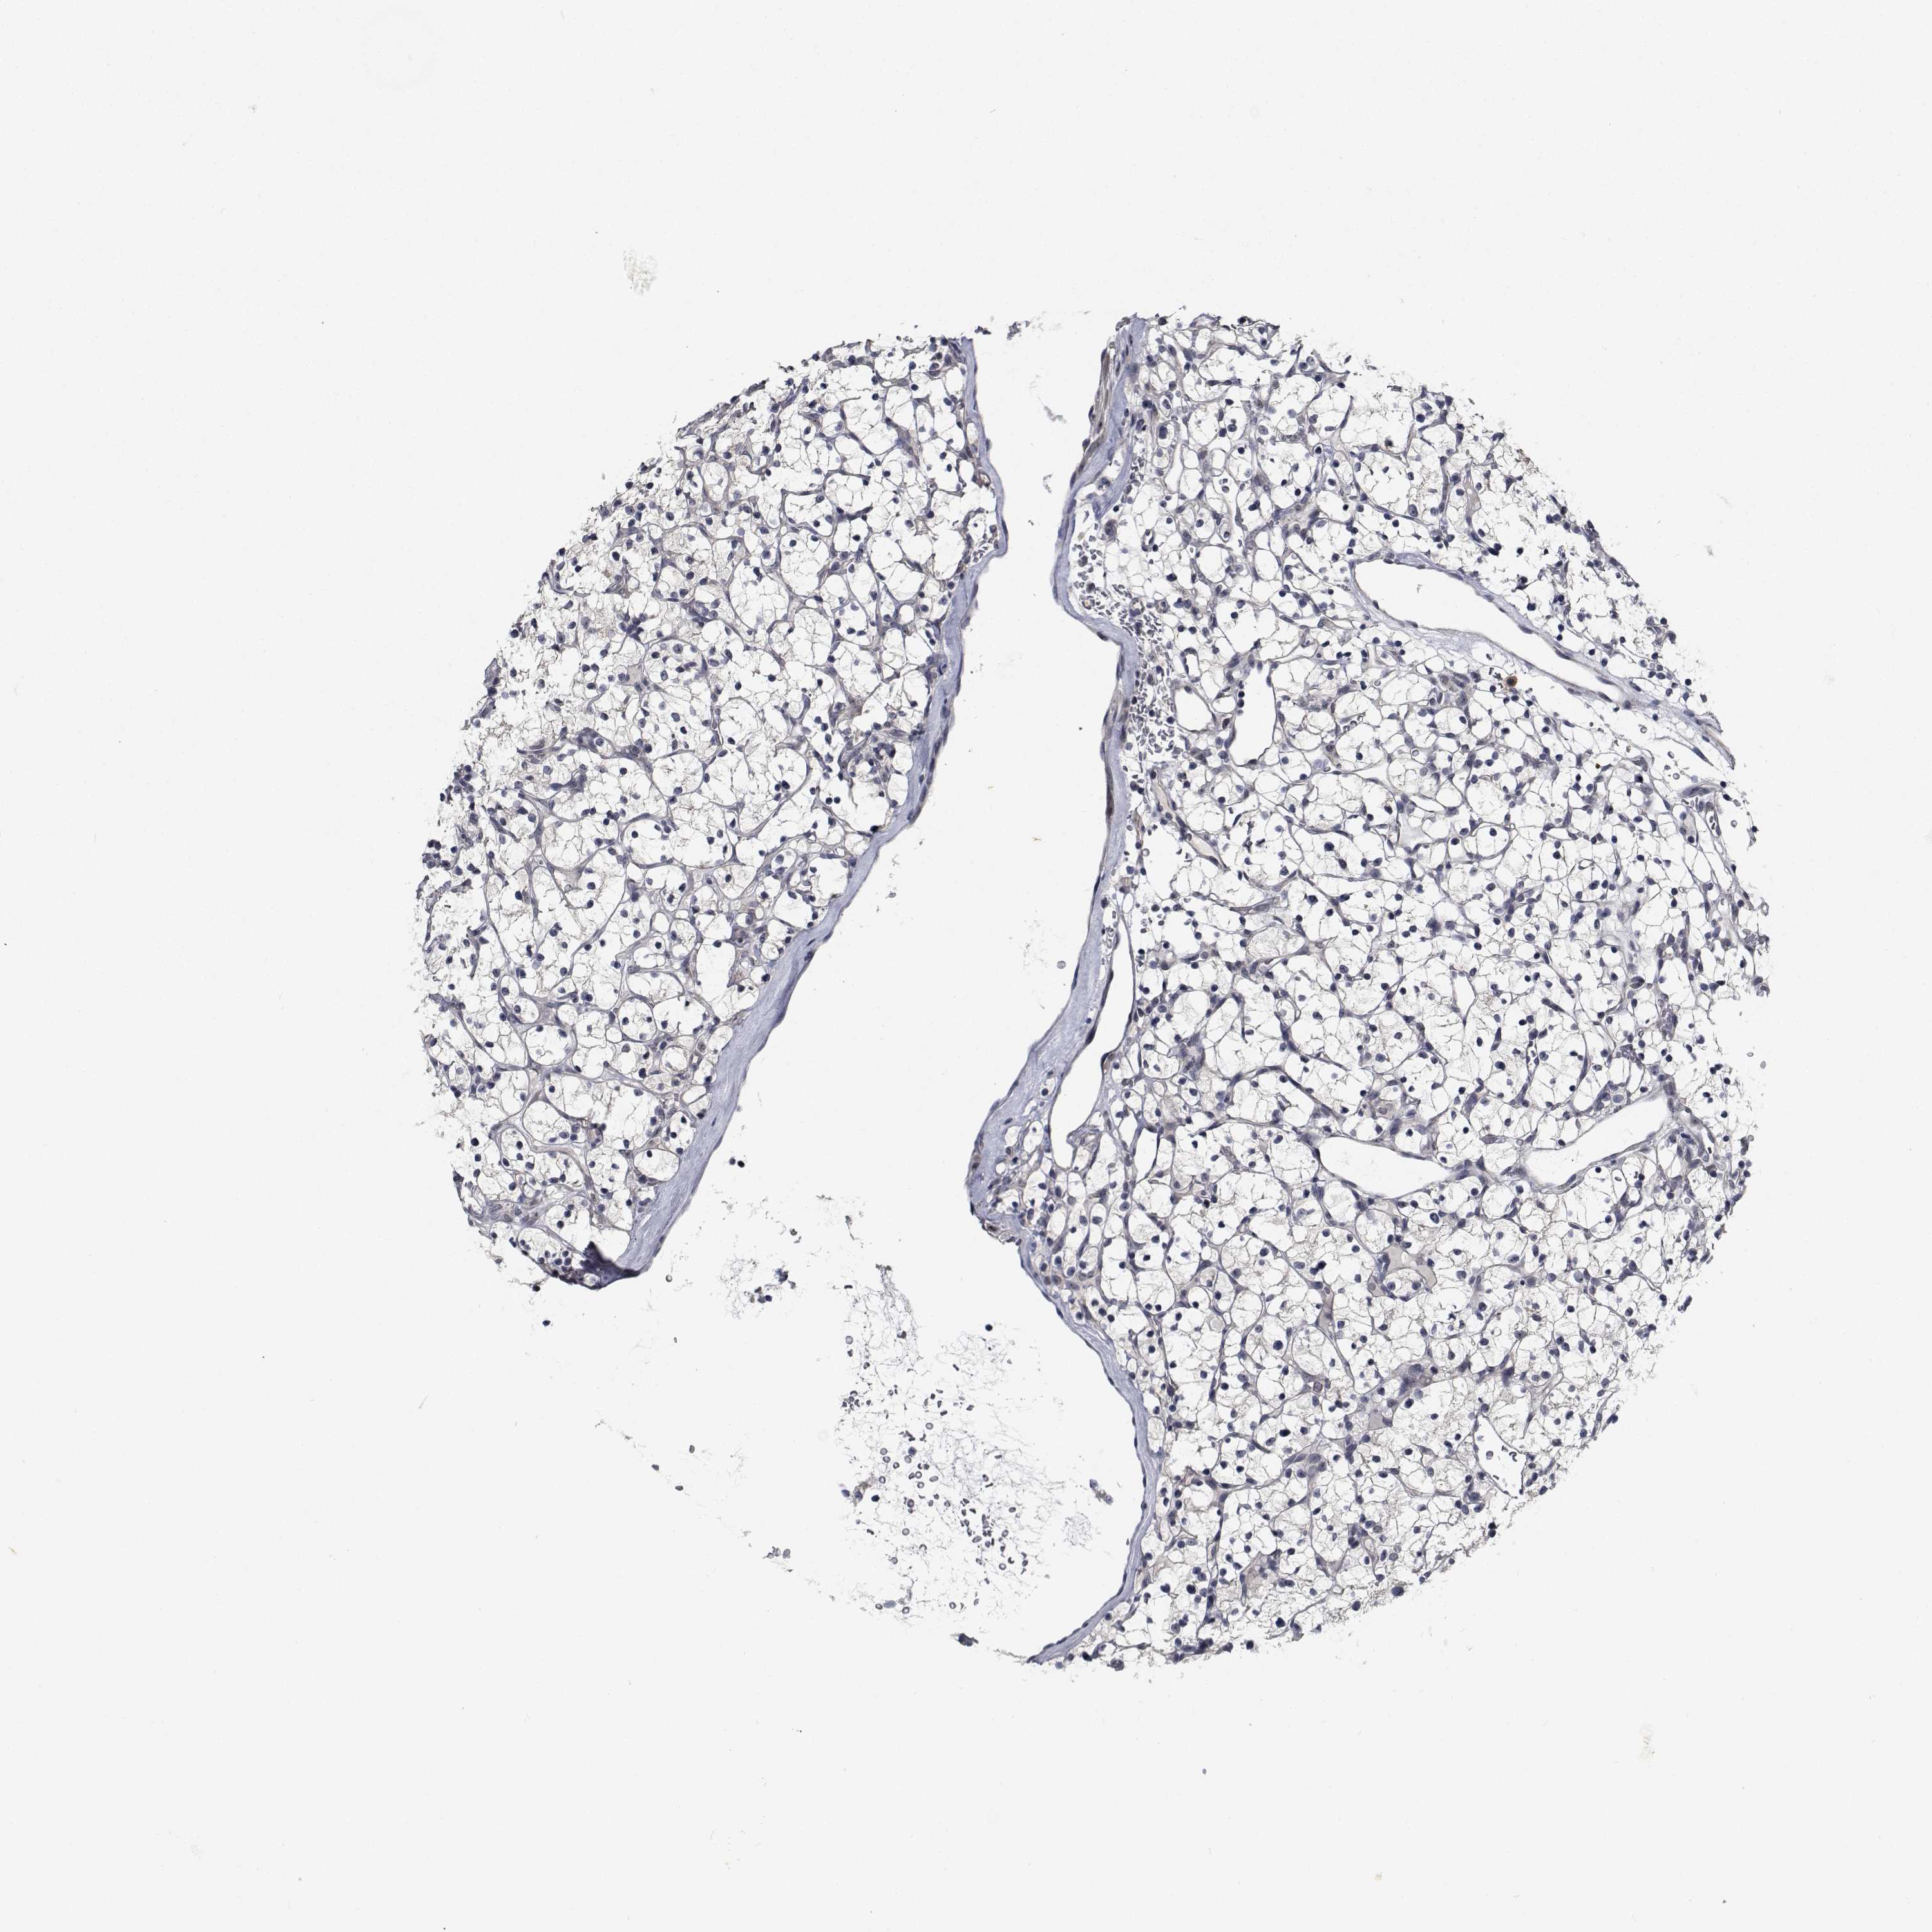

CANCER RENAL CANCER Show tissue menu

KICH TCGA KIRC TCGA KIRC VALIDATION KIRP TCGA PROTEIN RCC CPTAC PROTEIN EXPRESSION